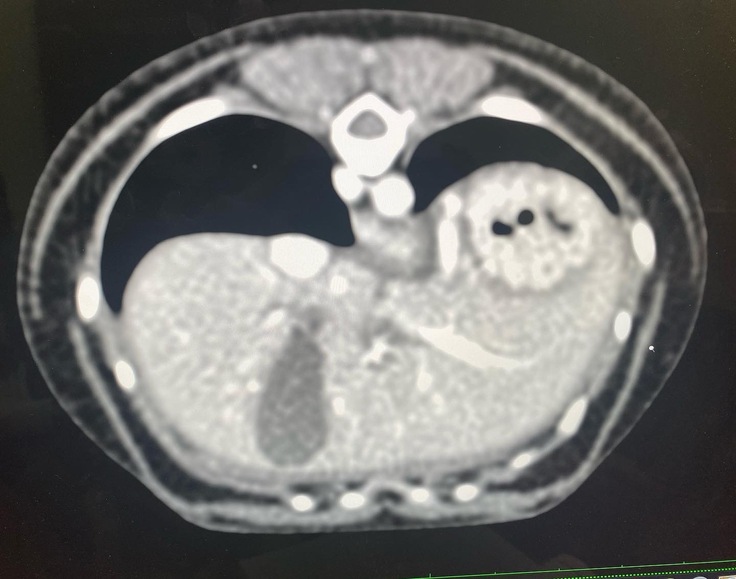

↓この診察内容で門脈体循環シャントを

先生が発見して下さいました。

○↑に載せてある診療明細書の腹部超音波エコー・x線検査の結果

↓CTの結果です

○↑に載せてある全身麻酔によるCT検査CTで2本の太いシャント血管があった事

シェリーの場合はシャント血管2本見つかりました。手術1回の可能性50%2回以上の可能性50%との事でした。